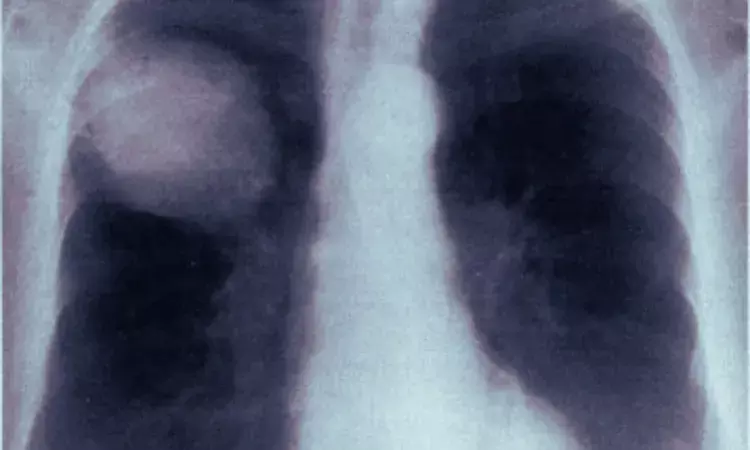

The case involved a 52-year-old male who underwent dual-port VATS for right upper lobectomy and right lower lobe superior segmentectomy to treat invasive pulmonary adenocarcinoma. On the second postoperative day, just two hours after chest tube removal, the patient experienced a sudden onset of profuse sweating, chest tightness, and difficulty breathing. Emergency chest X-rays showed complete lung atelectasis, and subsequent multidetector CT scans with flexible bronchoscopy confirmed incomplete torsion affecting the right middle and lower lobes.

Rather than proceeding directly to high-risk surgical reintervention, the medical team implemented a novel multimodal conservative strategy. This included selective intrabronchial air insufflation every 48 hours, noninvasive positive pressure ventilation via BiPAP, and maintenance of closed thoracic drainage. By postoperative day seven, three-dimensional imaging showed marked resolution of atelectasis, allowing safe removal of the chest tube. Follow-up imaging at three months demonstrated full re-expansion of the residual right lung, and two-year follow-up confirmed sustained lung function without any long-term complications.